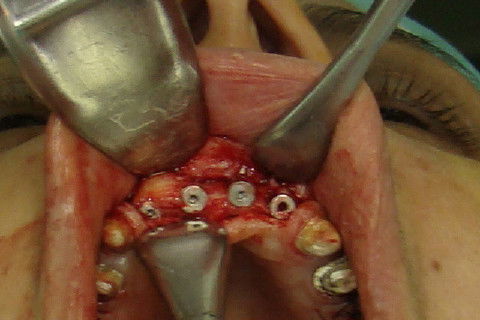

Marcação atraves do guia cirúrgico das posições dos implantes

Colocação dos implantes nas regiões 12 e 22 e perfuração das regiões 11 e 21

Vista oclusal dos 4 implantes colocados

Preenchimento dos espaços existentes com osso particulado e proteção com membrana de colageno

Sutura da região anterior da maxila